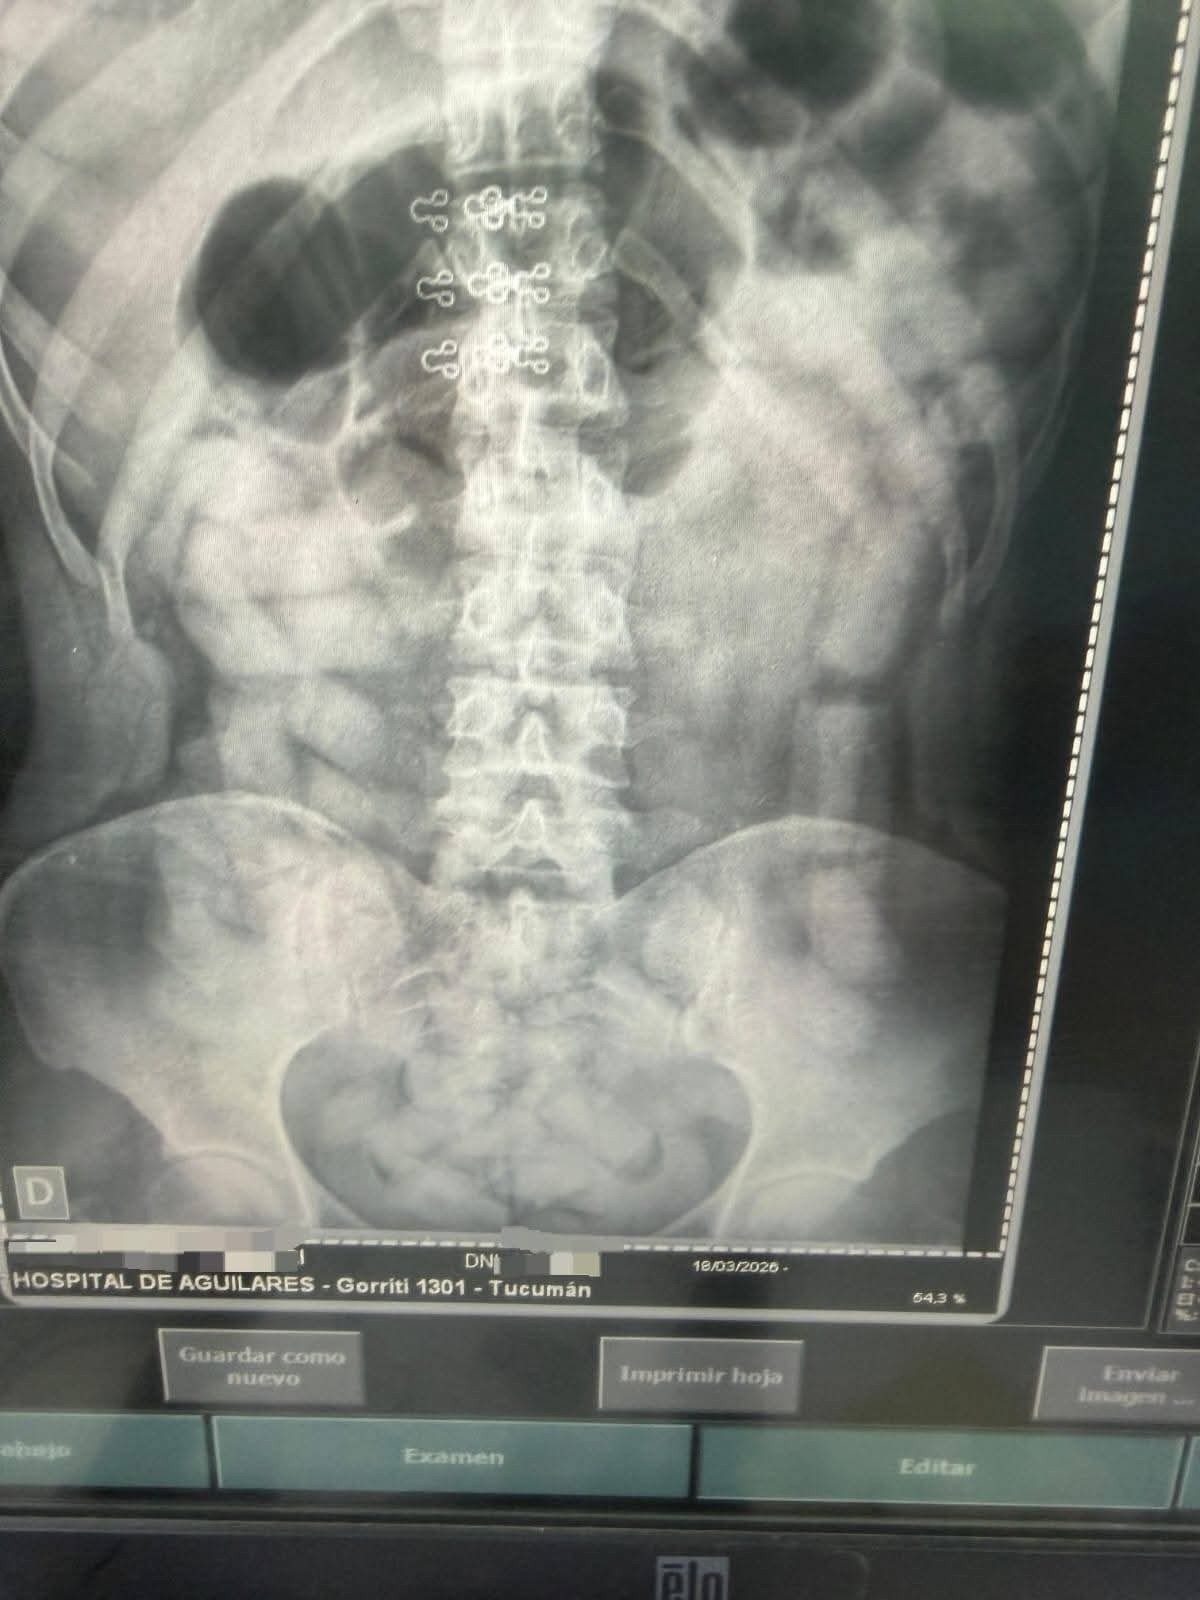

Ante la sospecha de tráfico de estupefacientes, se solicitó la intervención de personal médico.

Fue entonces cuando se confirmó que varios de los ocupantes trasladaban cápsulas de cocaína, algunas ocultas entre sus pertenencias y otras ingeridas, lo que derivó en un procedimiento más complejo que incluyó asistencia sanitaria.

El procedimiento continúa en desarrollo, ya que algunos de los involucrados permanecen bajo control médico mientras finaliza el proceso de extracción de las cápsulas ingeridas.